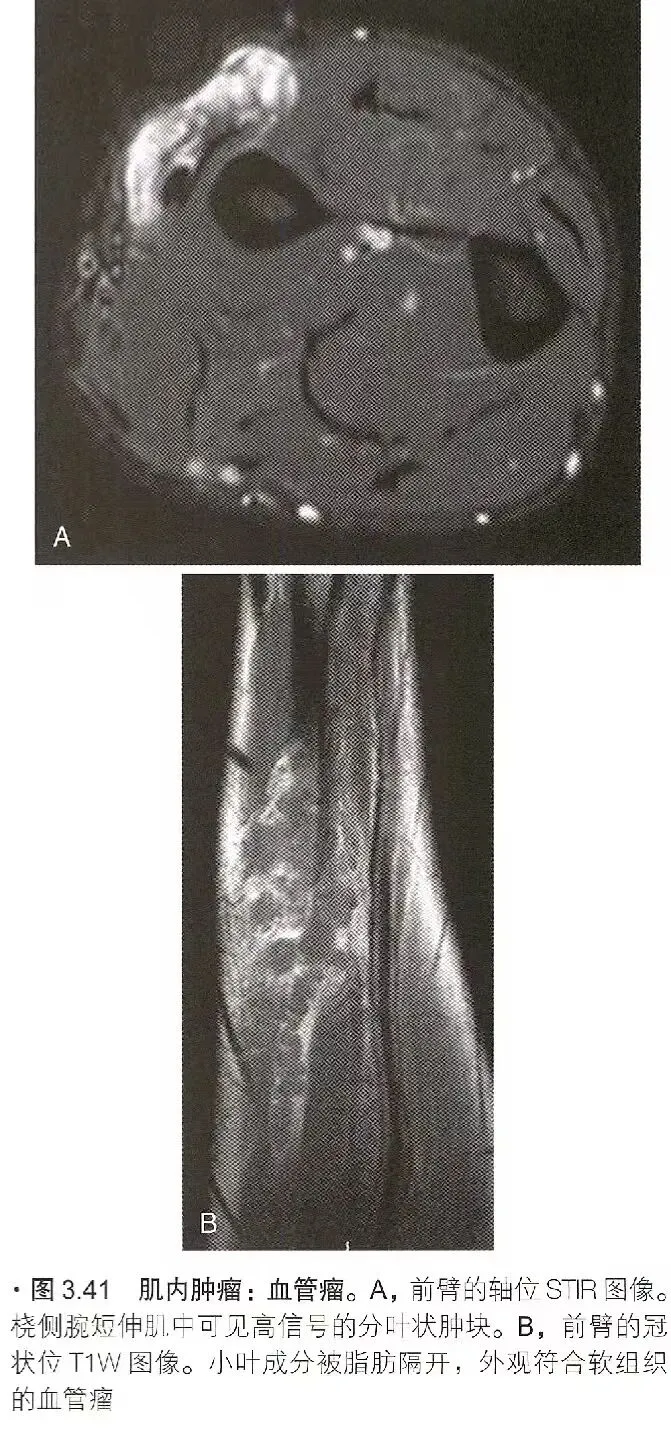

肿瘤